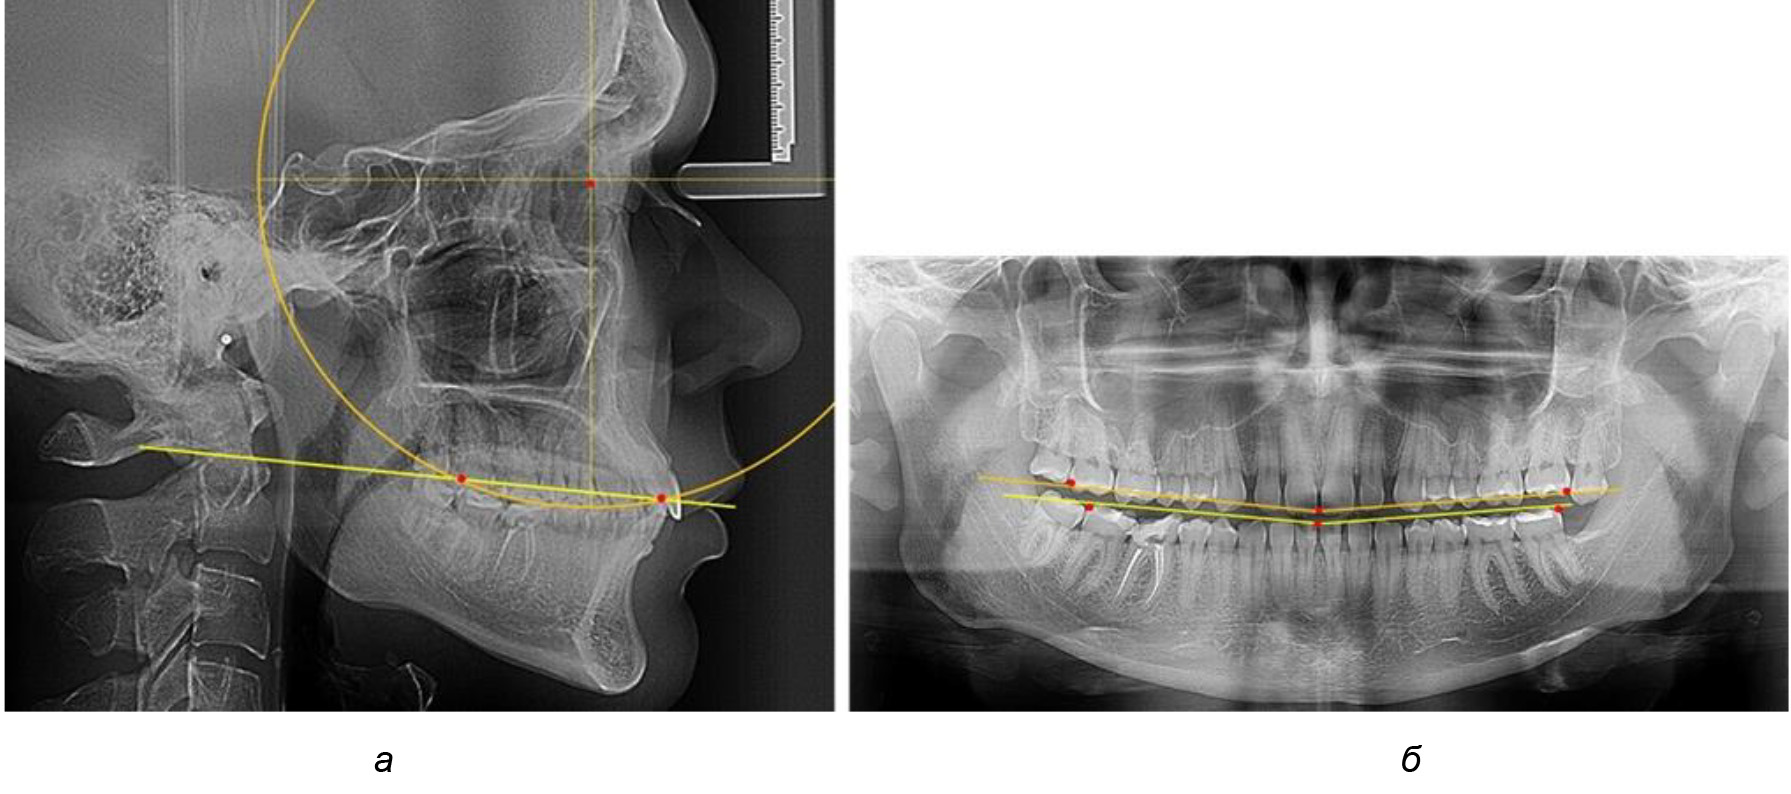

При анализе латеральных ТРГ устанавливали реперный окклюзионные точки в переднем и боковом отделе. Передняя точка устанавливалась на режущем крае нижнего медиального резца, которую в клинике ортодонтии обозначают как vPOcP. Дистальная точка второго нижнего моляра обозначалась как hPOcP. Измеряли расстояние между окклюзионными точками, что определяло сагиттальный размер окклюзионной линии. Использование программ PowerPoint позволило проводить окружность, проходящую по линии смыкания зубов через окклюзионные точки. Измеряли радиус окружности. Учитывая вариабельность размеров окклюзионной линии и радиуса окружности, определяли относительный показатель через отношение радиуса круга к длине сагиттального размера окклюзионной линии. Глубину окклюзионной кривой измеряли от точки наибольшей выпуклости до окклюзионной линии (рис. 1). На ортопантомограмме (ОПТГ) также соединяли окклюзионные точки правой и левой стороны и измеряли глубину окклюзионной кривой от точки наибольшей выпуклости до окклюзионной прямой линии. Результаты глубины кривой Spee сравнивали по данным ТРГ и ОПТГ.

Рис. 1. Метод определения кривой Spee на ТРГ (а) и на ОПТГ (б)